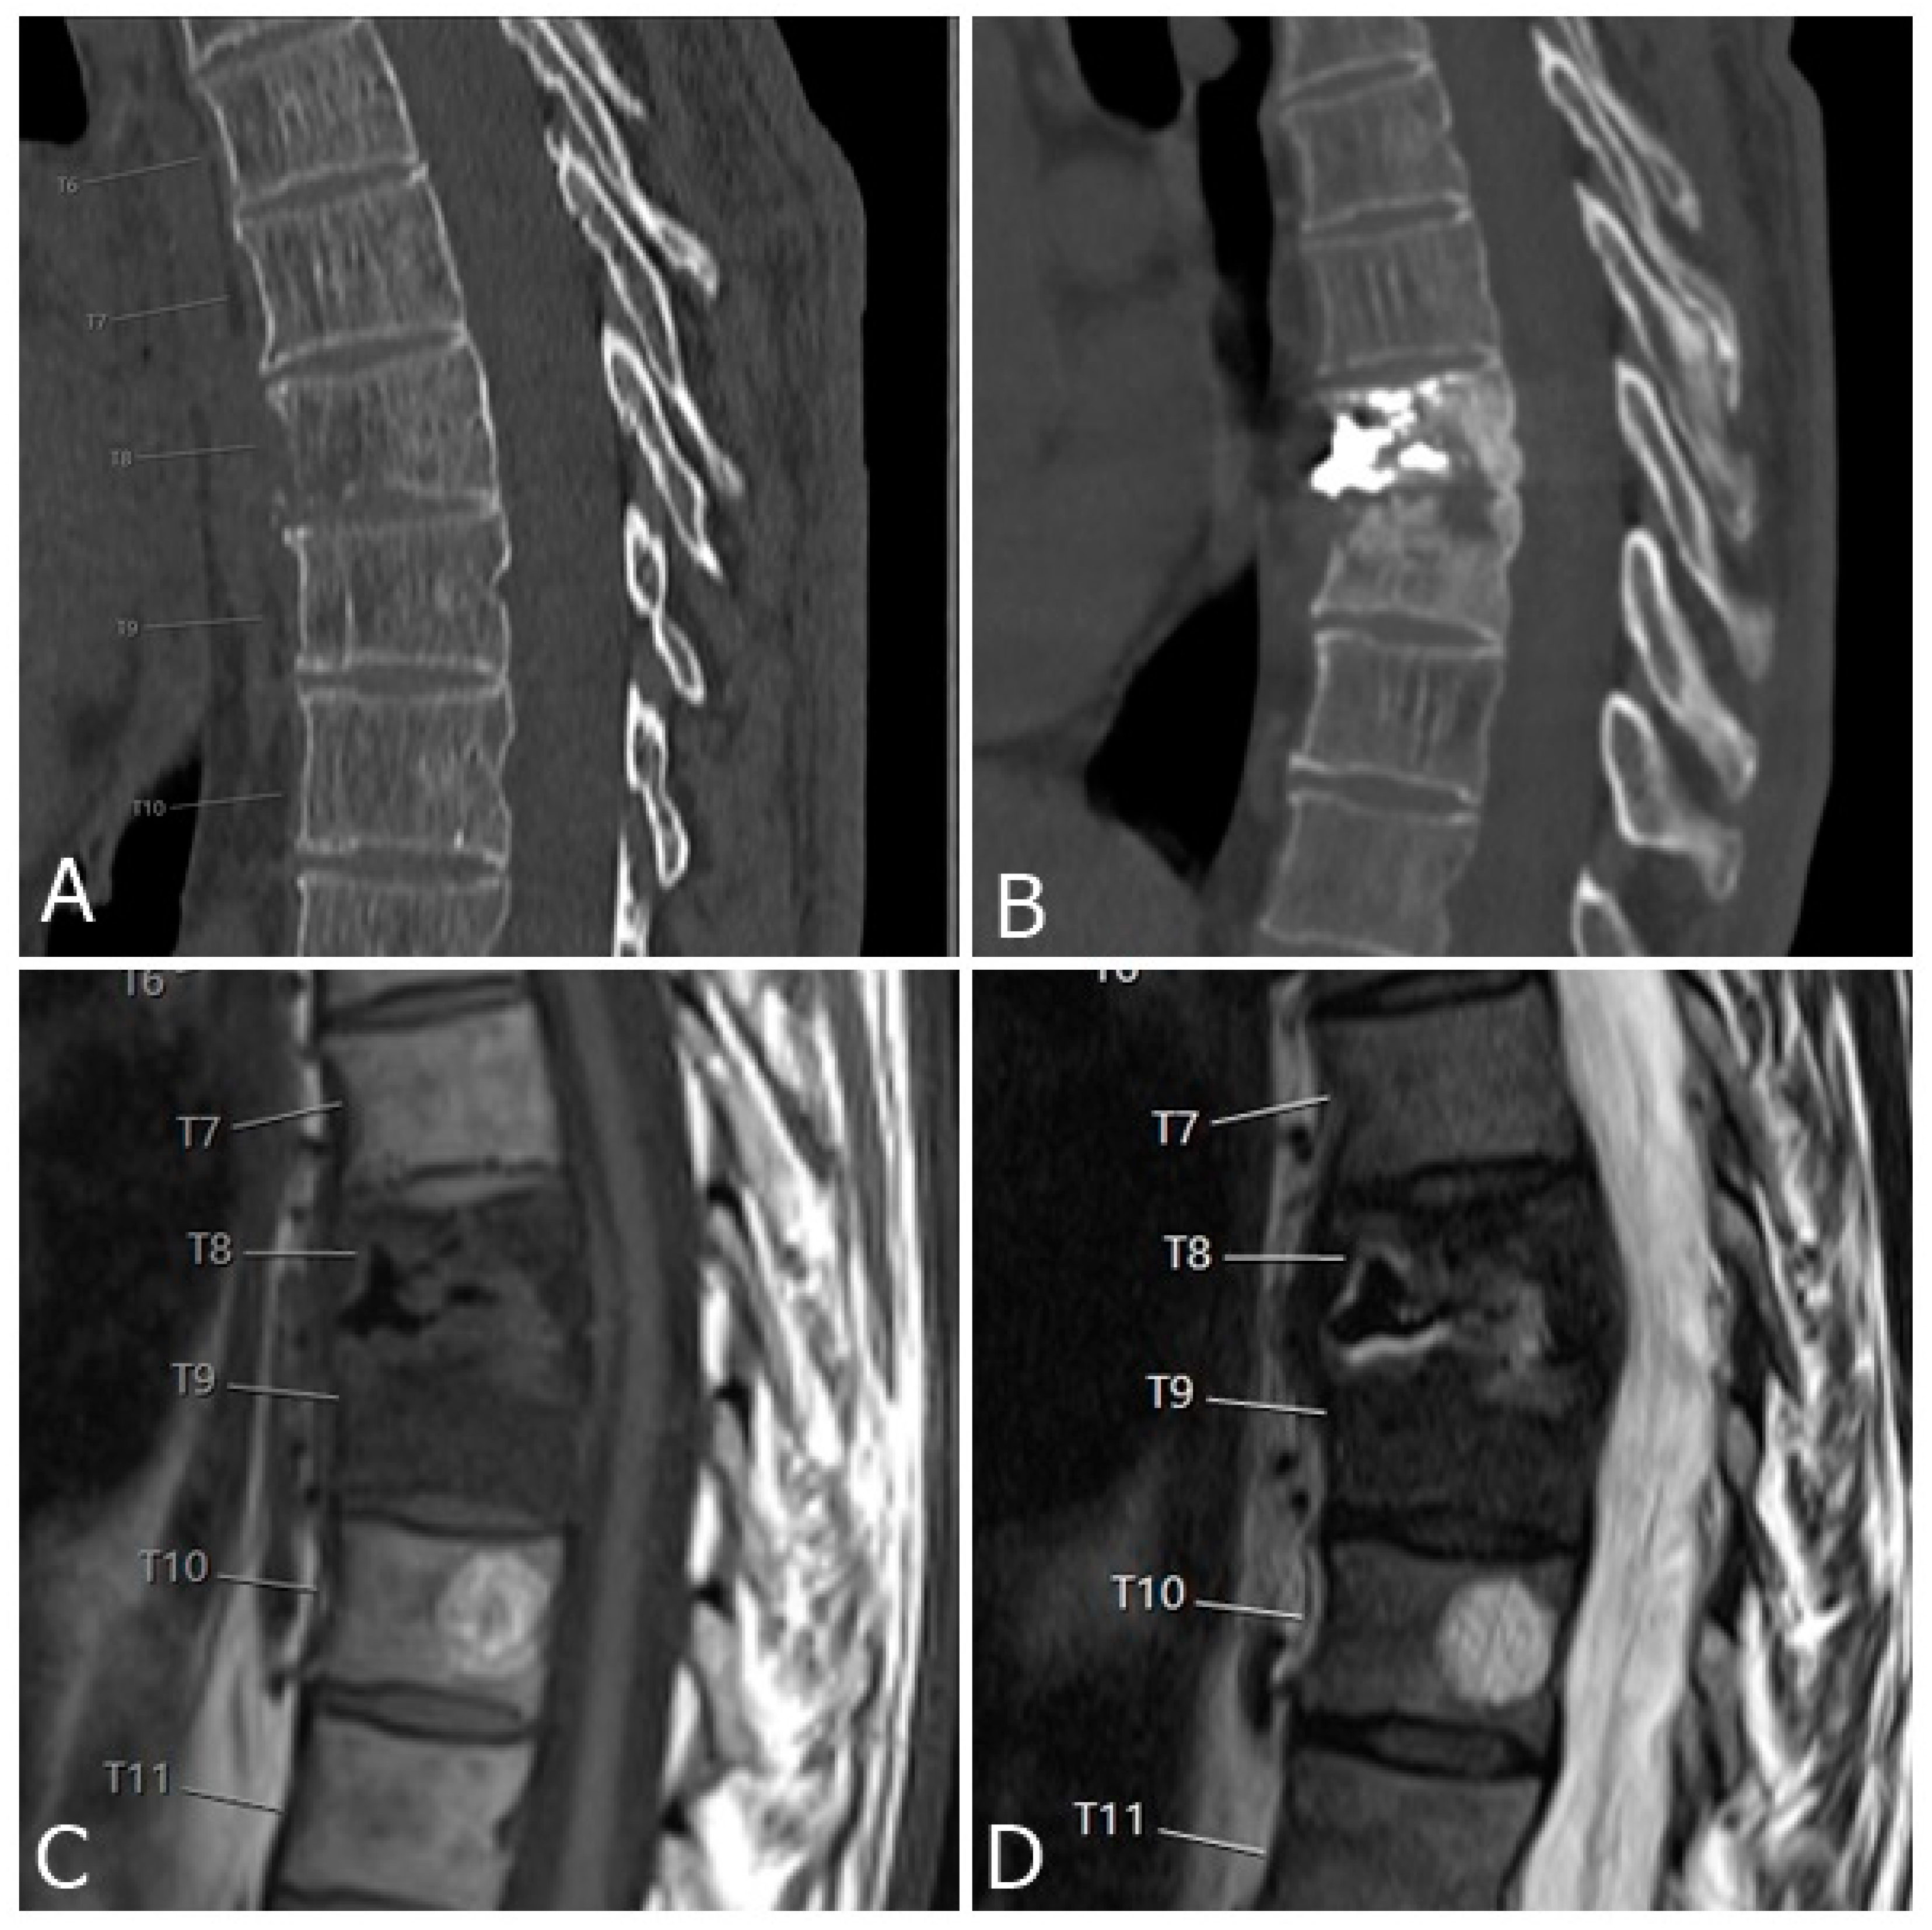

3.1. Epidural and Foraminal Cement Leakage